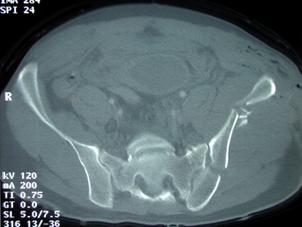

Fractura Malgaigne Fractura Malgaigne. Imagine CT

Fractura de

aripa iliaca stanga Fractura de aripa iliaca

stanga

Disjunctie sacro-iliaca stanga Disjunctie

sacro-iliaca stanga Aspect CT